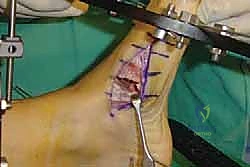

2. الشق الجراحي والوصول للمفاصل

يتم عمل شق جراحي واحد أو شقين (أحدهما في الجزء العلوي الداخلي والآخر في الجزء الخارجي) للوصول إلى مفاصل منتصف القدم دون الإضرار بالأوتار الحيوية والأعصاب والأوعية الدموية. يتم استخدام تقنيات الجراحة الدقيقة (Microsurgery) للحفاظ على الأنسجة المحيطة السليمة.

لضمان التحام العظام لتصبح عظمة واحدة صلبة، يجب تثبيتها بقوة هائلة حتى لا تتحرك أثناء فترة الشفاء. يتم استخدام مسامير معدنية متطورة (Screws)، أو شرائح معدنية خاصة (Plates)، أو دبابيس طبية متخصصة (Staples) مصنوعة من التيتانيوم الآمن على الجسم.

7. الإغلاق والضماد

بعد التأكد التام من وضع العظام وثباتها باستخدام جهاز الأشعة السينية داخل غرفة العمليات (C-Arm)، يتم إغلاق الشقوق الج